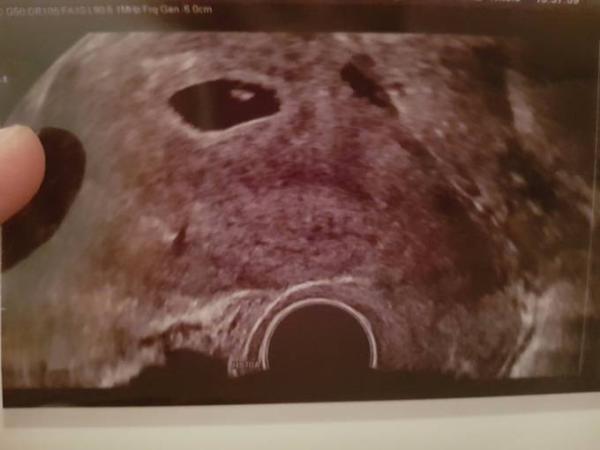

Hey ihr Lieben Hatte heute meinen zweiten Termin .. Haben unser Baby das erste mal gesehen und mit Herzschlag ..ich musste fast weinen Mein nächster Termin in 4 Wochen Ein Bild gibt es auch dazu Wie ich gelesen habe haben diese Woche ein paar andere Mädels ihren FA Termin ich wünsche euch alles gute

Bild zu 2. FA Termin - Forum für Februar - Mamis